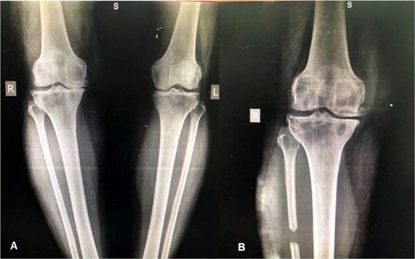

Подобно высокой остеотомии большеберцовой кости проксимальная корригирующая остеотомия малоберцовой кости может облегчить симптомы медиального остеоартроза с перестройкой нижней конечности. Однако, хотя исправление оси конечности является основной целью высокой остеотомии большеберцовой кости, принцип проксимальной корригирующей остеотомии малоберцовой кости исходит из теории «неравномерного распределения».

Как следствие поддержки малоберцовой костью, «неравномерный» означает, что давление на плато большеберцовой кости является асимметричным, причем давление на медиальном плато более выражено, чем на латеральном плато. В конце концов, медиальное плато становится значительно ниже латерального, и в нижней конечности возникает варусная деформация. Эти изменения механической оси приводят к концентрации напряжений в медиальном компартменте и дегенерации хряща и мениска, которые являются основными патологическими проявлениями медиального остеоартроза. Таким образом, при «неравномерном распределении большеберцовой кости» медиальный остеоартроз можно также назвать «синдромом дисбаланса в коленном суставе».

Проксимальная корригирующая остеотомия малоберцовой кости ослабляет боковую поддержку малоберцовой кости и приводит к коррекции варусной деформации, которая впоследствии может смещать направление нагрузки от медиального отдела в сторону латерального отдела, что приводит к уменьшению боли и удовлетворительному функциональному восстановлению.